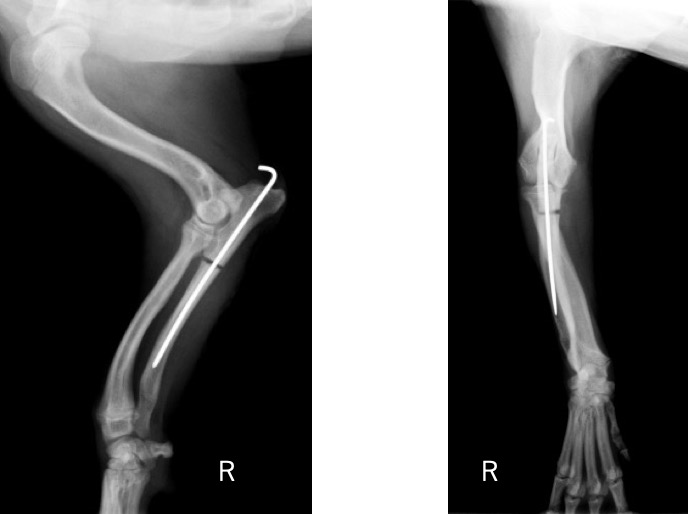

術後の側面像と頭尾側像 (骨切り後に尺骨のアラインメントを合わせるために髄内ピンとして1.2mm K-wireを刺入しました)